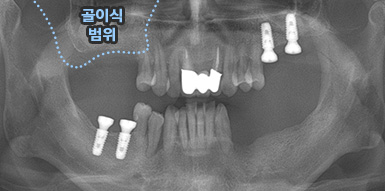

치주염 등으로 치조골(잇몸뼈)의 양이 부족한 경우

치조골 이식술을 통하여 충분한 뼈의 양을 확보한 후

임플란트를 식립합니다.

뼈의 밀도가 치밀하고 단단하며, 양이 충분할수록 임플란트의 성공률이 높아집니다.

청담네오플란트는 풍부한 경험의 의료진이 치조골 이식술을 통해 치조골을 적절한 양과

밀도로 재생시킨 후 임플란트를 식립합니다. 뼈의 흡수가 심하지 않아 적은 양의

치조골 이식을 하는 경우 임플란트 식립을 동시에 진행할 수 있지만, 뼈의 흡수가

심하여 많은 양의 치조골 이식이 필요한 경우 치조골 이식술을 먼저 진행한 후,

치조골이 재생되면 임플란트를 식립하여 보다 정밀하고 안전한 시술 결과를 얻을 수 있습니다.

치조골 이식술 전후사진

B

A